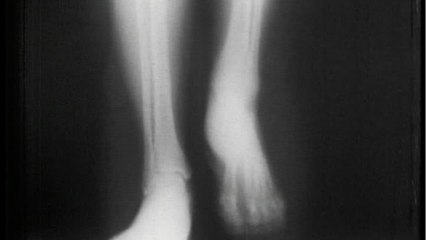

Corona has troubled people a lot. Even after being free from infection, the patients are not recovering completely. They are facing different kinds of problems. Till a few days ago, cases of black fungus were being seen more in patients who were cured of corona and now a new threat is looming on such people, whose name is avascular necrosis. It is also known as 'Death of Bone'. Three cases have been reported in Mumbai. Experts say that this could be the next debilitating condition in patients recovering from corona after the outbreak of mucormycosis.